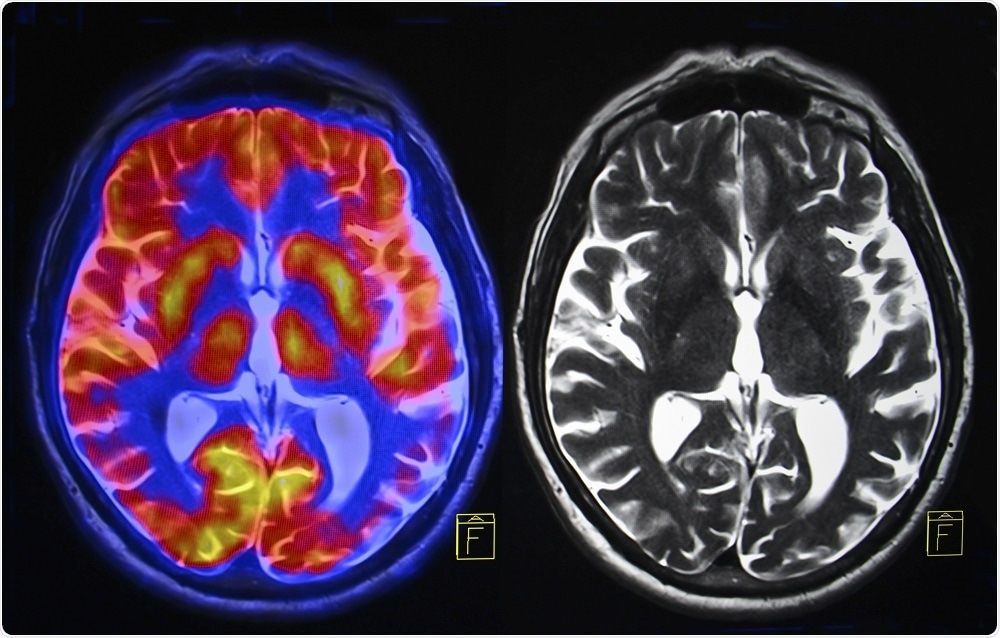

Credit:Semnic/Shutterstock.com